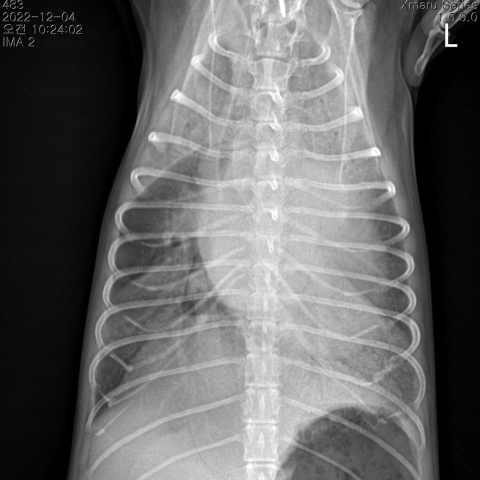

¿ì¸® ¾ÆÀÌÀÇ Ä´Ä´°Å¸²ÀÌ, »êÃ¥À» Èûµé¾îÇÏ´Â Áõ»óÀÌ ´Ü¼øÈ÷ ³ªÀ̰¡ µé¾î¼ À̱⠶§¹®Àϱî¿ä? ½ÉÀ庴Àº ³ë·É°ß 10¸¶¸® Áß 6¸¶¸®¿¡¼ ³ªÅ¸³ª´Â ÈçÇÑ ÁúȯÀÔ´Ï´Ù. ÆÇ¸·ÀÇ º¯¼ºÀ¸·Î ÀÎÇØ ½ÉÀåÀÌ Ä¿Áö¸é ±âħ, ¼ö¸é ½Ã È£Èí¼ö Áõ°¡ µîÀÇ ÀÓ»óÁõ»óÀÌ ³ªÅ¸³¯ ¼ö ÀÖ½À´Ï´Ù. °ü¸®µÇÁö ¸øÇÏ¸é ÆóºÎÁ¾À¸·Î ÀÎÇÑ È£Èí±â ÀÀ±Þ»óȲÀÌ »ý±æ ¼ö ÀÖ½À´Ï´Ù. ÀûÀýÇÑ °Ë»ç¸¦ ÅëÇØ ½ÉÀ庴 ´Ü°èº° °ü¸®¸¦ ¹Þ¾Æ¾ß ÇÕ´Ï´Ù.

½Åü°Ë»ç¸¦ ÅëÇØ ½ÉÀâÀ½ÀÌ Ã»Áø µÇ¸é ,ÈäºÎ ¹æ»ç¼±°Ë»ç, ½ÉÀå ÃÊÀ½ÆÄ, BNP°Ë»ç, Ç÷¾Ð°Ë»ç¸¦ ½Ç½Ã ÇÕ´Ï´Ù. À̸¦ ¹ÙÅÁÀ¸·Î °¢ ´Ü°èº° ½ÉÀ庴 °ü¸®¸¦ ÁøÇàÇÕ´Ï´Ù.

¿ïÇ÷¼º ½ÉºÎÀü

ÆóºÎÁ¾